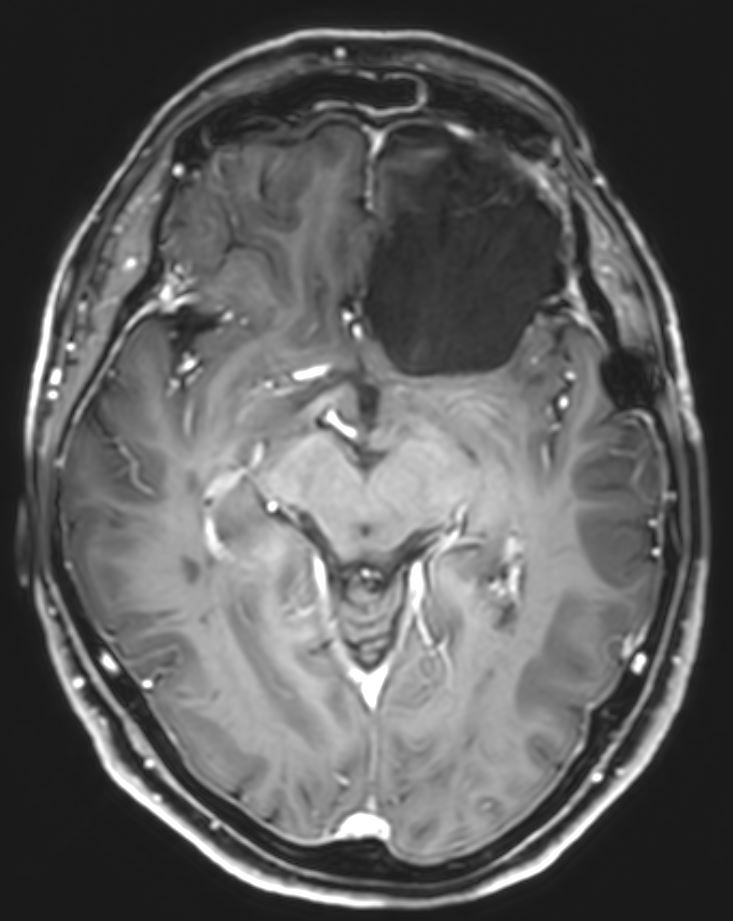

Ο απεικονιστικός έλεγχος με μαγνητική τομογραφία ανέδειξε ευμεγέθη όγκο της πτέρυγας του σφηνοειδούς αριστερά, συμβατό με μηνιγγίωμα.

Η μετεγχειρητική μαγνητική τομογραφία εγκεφάλου δείχνει ολική εξαίρεση. Η ιστολογική εξέταση ανέδειξε μηνιγγίωμα (WHO I).